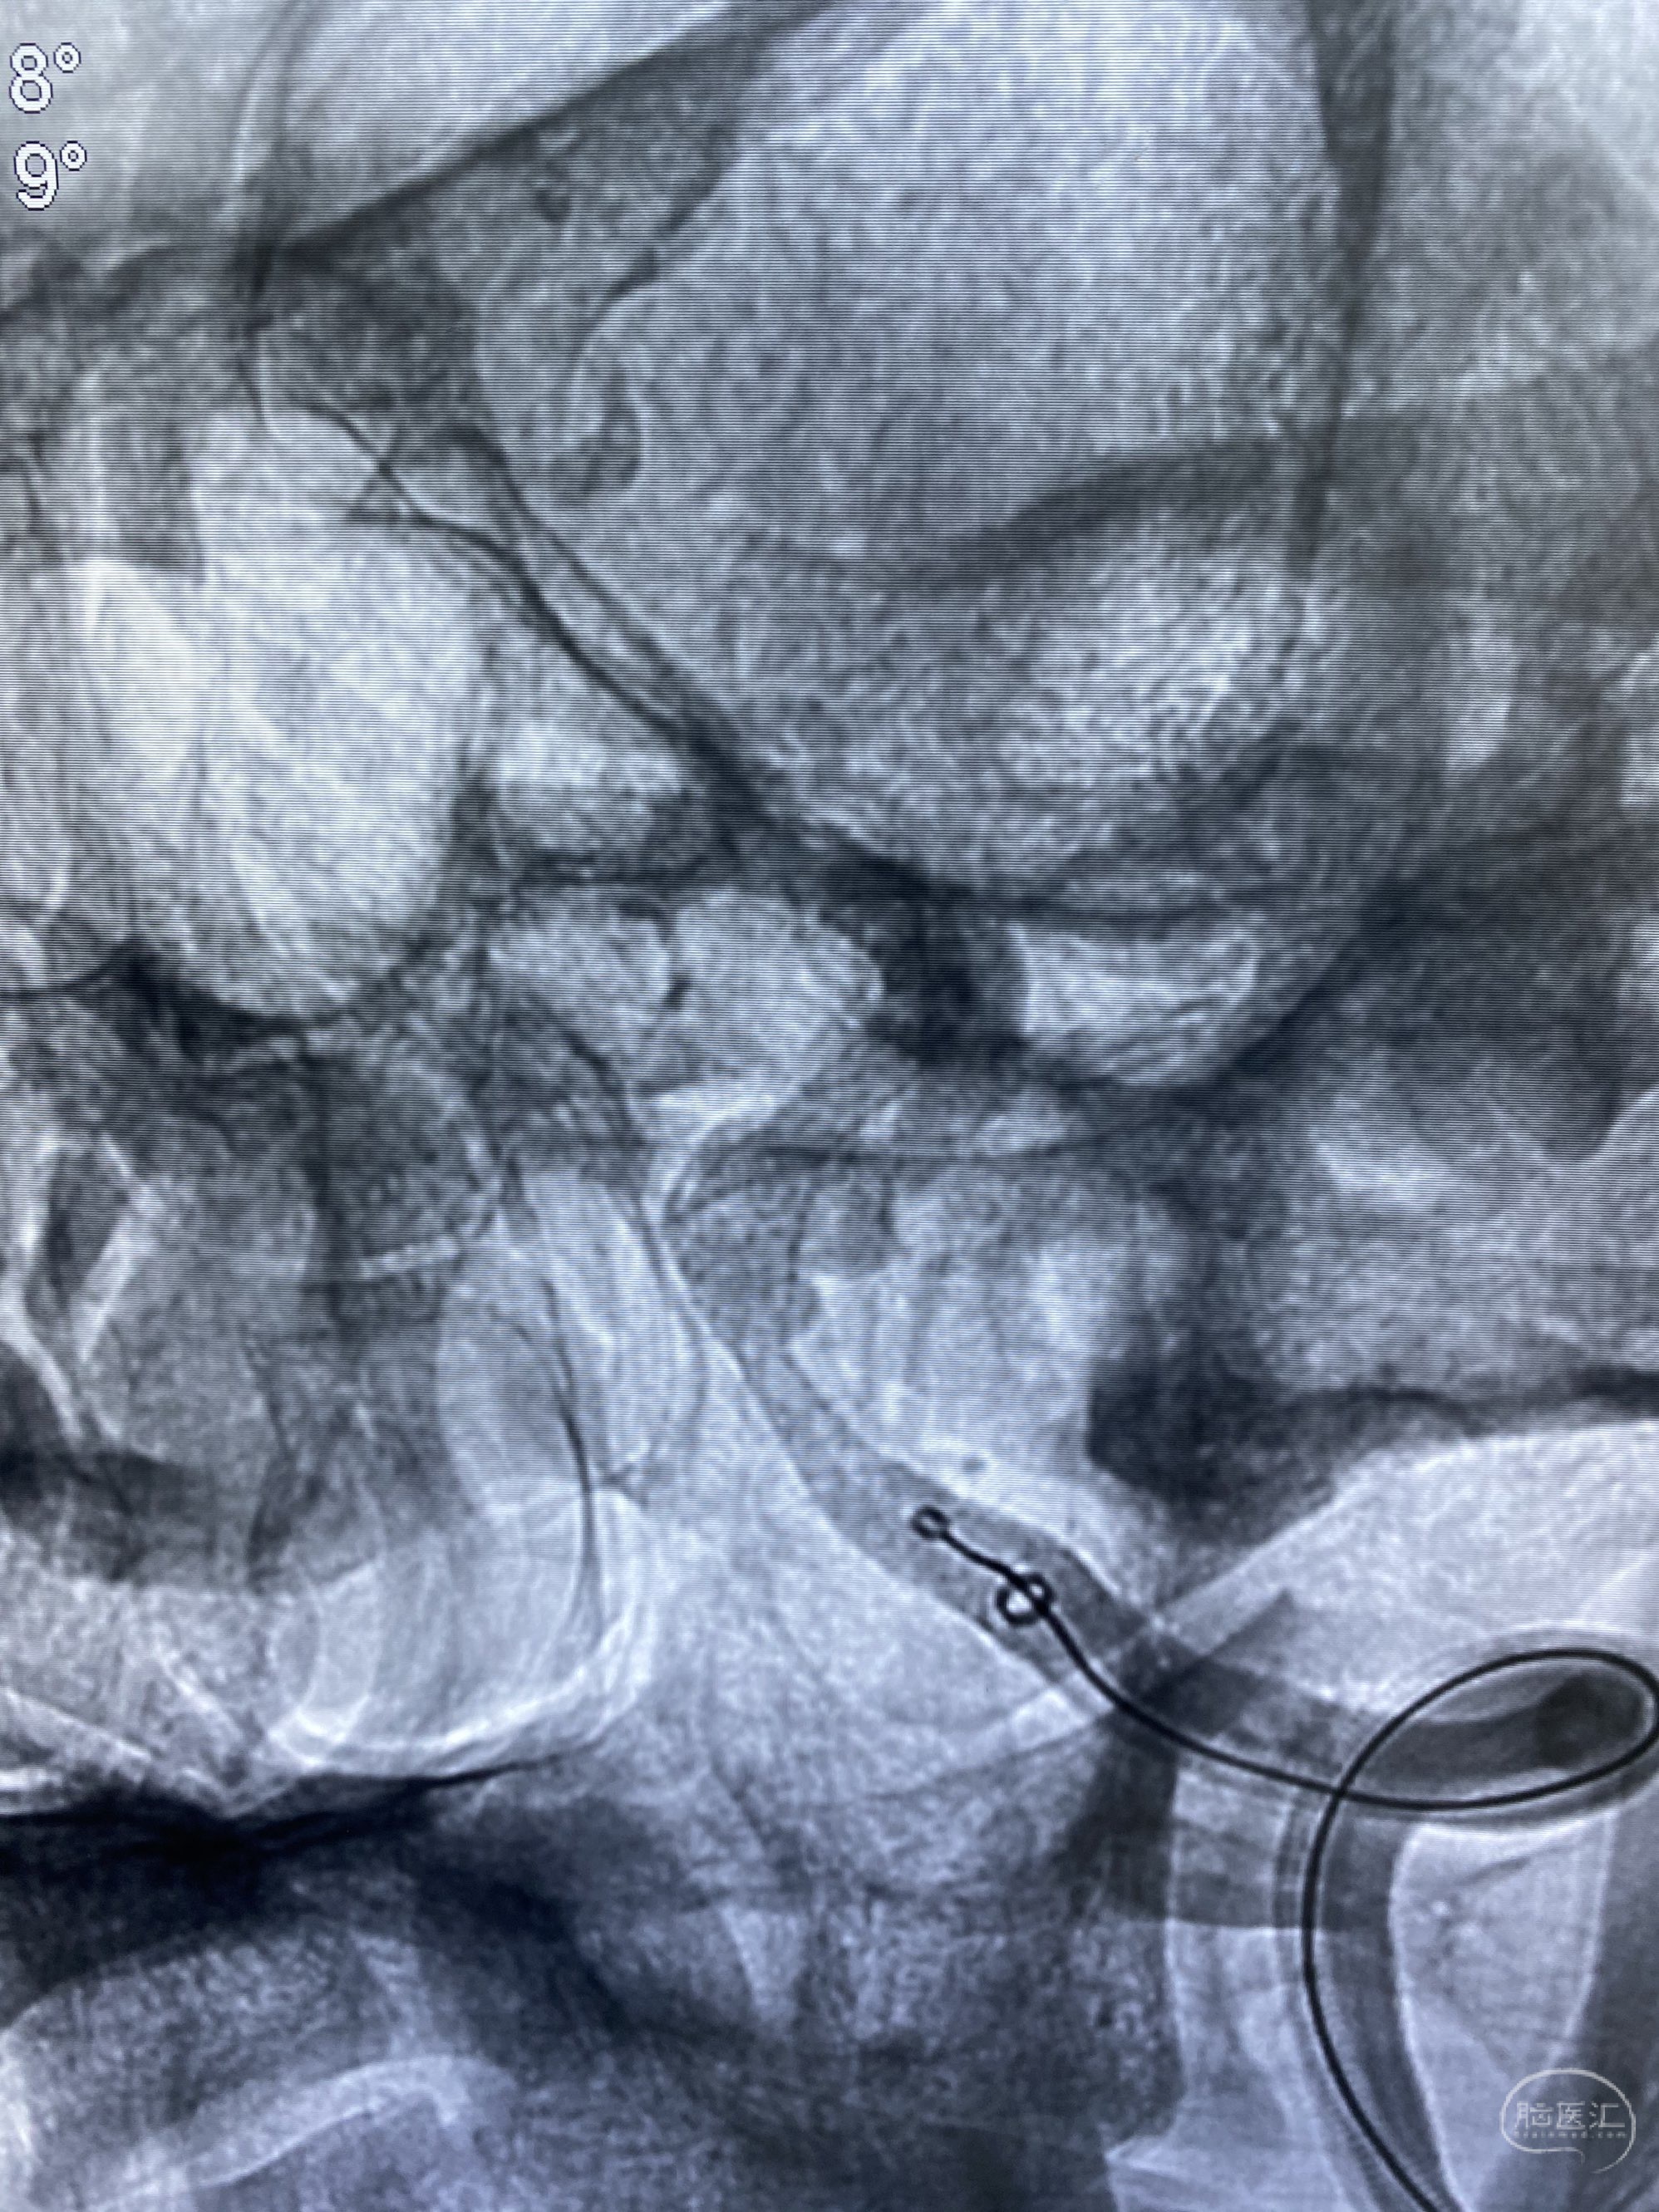

今日手术,TJG,M62Y,一期左侧颈动脉狭窄支架植入,二期椎动脉V4段多发夹层动脉瘤伴狭窄,常规支架辅助栓塞方法复杂又危险,血流导向装置植入快捷又安全。南阳市中心医院神经内科脑血管病介入团队pipeline flexFD植入两人导师资格。

椎动脉颅内段多发夹层动脉瘤伴载瘤动脉狭窄pipeline flex植入

今日手术,TJG,M62Y,一期左侧颈动脉狭窄支架植入,二期椎动脉V4段多发夹层动脉瘤伴狭窄,常规支架辅助栓塞方法复杂又危险,血流导向装置植入快捷又安全。南阳市中心医院神经内科脑血管病介入团队pipeline flexFD植入两人导师资格。